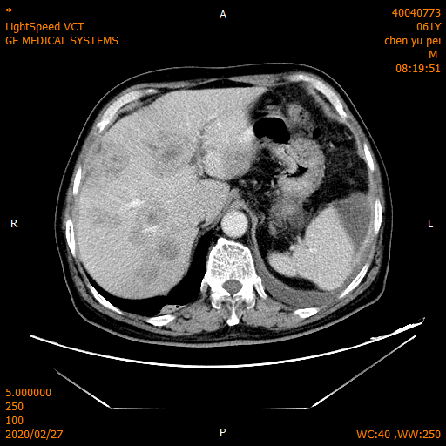

2020-02-04 CT

肝脏多发异常强化灶,考虑转移。

横结肠-降结肠交界处壁增厚强化,请结合消化道检查,腹腔部分肠管扩张积气积液,可见气液平,请结合临床。

2020-02-27 增强CT报告:

肝脏多个略低密度影,考虑转移灶,结合临床;脾脏外缘积液;

胆囊略大;前列腺钙化灶;腹腔积液;左中下腹术后改变;

腹盆腔、后腹膜多发淋巴结,局部肿大;双侧腹股沟小淋巴结。